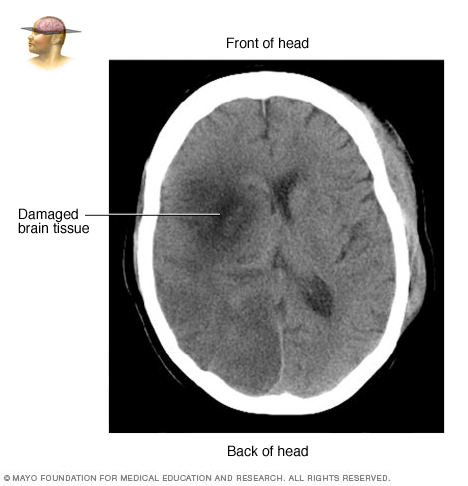

- Computerized tomography (CT) scan. A CT scan uses a series of X-rays to create a detailed image of your brain. A CT scan can show bleeding in the brain, an ischemic stroke, a tumor or other conditions. You might have a dye injected into your bloodstream to view the blood vessels in the neck and brain in greater detail. This type of test is called a computerized tomography angiography.

CT scan showing brain tissue damaged by stroke" />Treatment

Emergency treatment depends on whether you're having an ischemic or hemorrhagic stroke. During an ischemic stroke, blood vessels in the brain are blocked or narrowed. During a hemorrhagic stroke, there's bleeding into the brain.